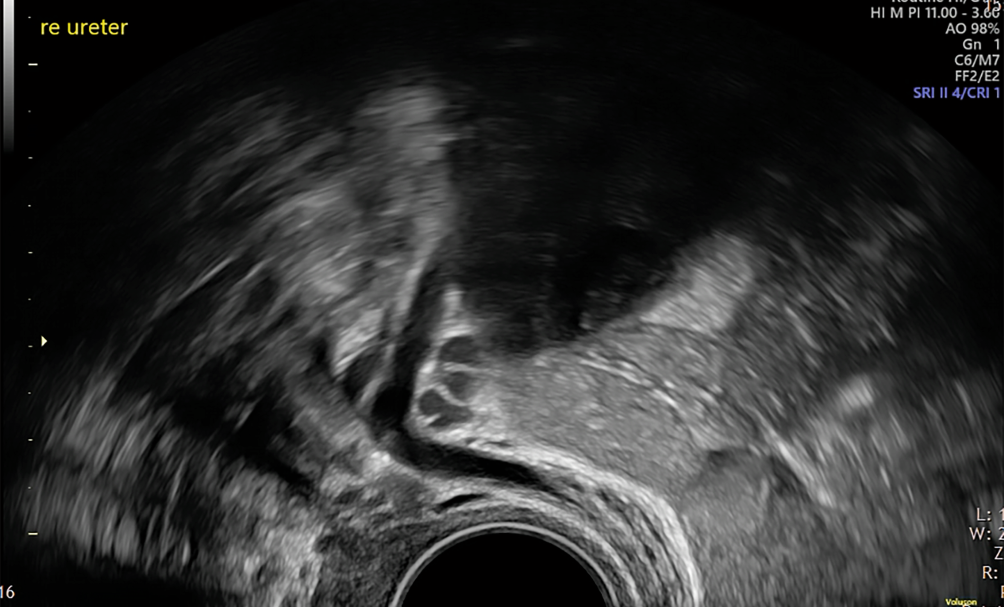

Diese Zeichen lassen sich in unserer Erfahrung mit wenig Übung bei praktisch allen Patientinnen darstellen und ermöglichen bereits nach wenigen Anwendungen eine völlig neue Orientierung im Bereich der Beckenwand. Darstellbar ist die gesamte peritoneale Oberfläche der Fossae ovaricae, wobei die anfangs erwähnten Einschränkungen zur Beurteilung des Peritoneums weiterhin gelten. Gelegentlich lassen sich dennoch kleinste Einschlusszystchen, winzige Auflagerungen auf der sonst glatten Oberfläche oder eine hyperechogene Verdickung als Zeichen einer Fibroseplatte darstellen. Direkt subperitoneal kann zudem der Verlauf der Beckengefässe sowie der Ureteren dargestellt werden (Abb. 4).

Abb. 4

Rechter Ureter im Bereich des „Ureterknies“. Medial davon ist das uterine Gefässbündel sichtbar. Man beachte die hyperechogene Linie als Teil des „tail sign“

Bild vergrößern

Eine Stauung (sichtbar z. B. durch einen grosslumigen Ureter oder einen Kalibersprung) oder Läsionen in diesem Bereich müssen genauestens abgeklärt und um eine Nierensonographie zum Ausschluss einer Stauung ergänzt werden; dies gilt für tiefe Endometriose im lateralen Kompartiment sowie für das Vorliegen von Endometriomen (Surrogatmarker für begleitende DE!). Klinisch entscheidend ist, ob es sich um eine extrinsische oder intrinsische tiefe Endometriose des Ureters handelt [12].